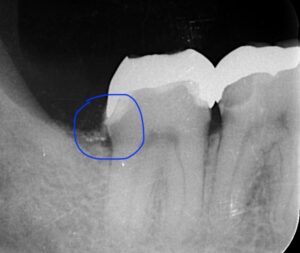

レントゲンの青丸の部分が被せ物の下の虫歯になります。

歯茎の中になりますので器具が入りません。